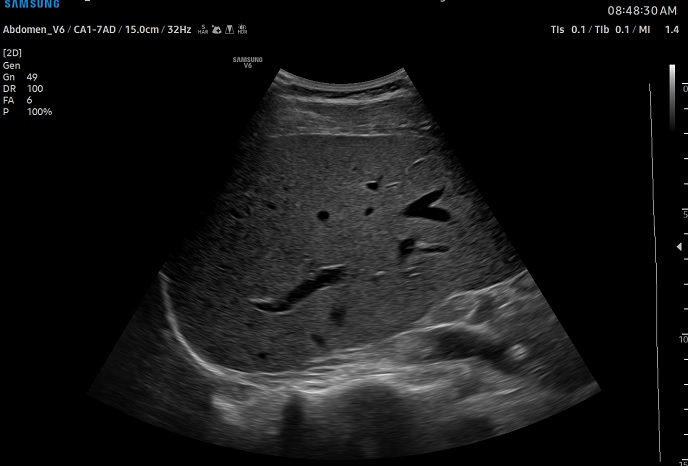

하이앤드 초음파 장비를

활용한 정밀 심장 검사

심장 질환 진단에서 가장 중요한 것은 ‘심장의 상태를 얼마나 정확하게 볼 수 있느냐’입니다. 저희 센터는 대학병원급 하이앤드 초음파 장비를 도입하여, 실시간 3D 렌더링으로 정밀 진단이 가능하며, 심장의 구조·혈류·기능을 실시간 고해상도로 관찰합니다.

미세한 판막 움직임, 혈류 속도 변화, 심방·심실 크기와 수축력까지 정밀하게 분석할 수 있어, 심장질환의 조기 발견과 치료 계획 수립에 큰 차이를 만듭니다.